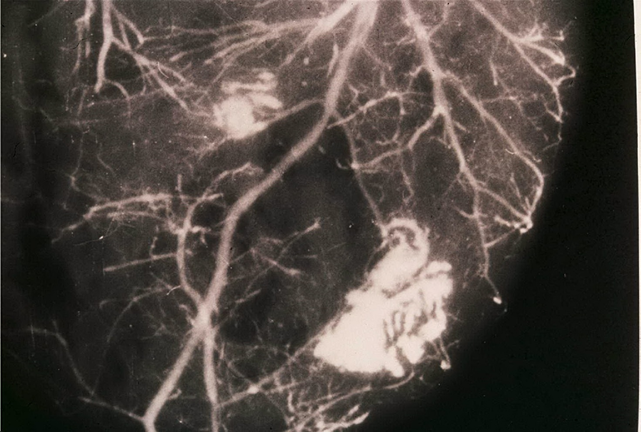

Techniques of study carried out by using post-mortem coronary injection with a radiopaque mass associated with a chemical digestion of myocardial mass permitted to obtain heart casts which give three-dimensional pictures of the coronary tree and, in addition, permit to identify cardiac alterations of both heart and coronary vessels (Figures 1-3).

Figure 1 Post-mortem angiography obtained by using barium sulfate combined with bacto-gelatin of a part of myocardial mass in a heart cast. There is evidence of coronary collaterals, intercoronary and intracoronary anastomoses as well as an avascular area in the central zone of the left ventricular wall due to an old myocardial infarction (white arrows). Reproduced from Aurelio Leone:13 Anatomy of the Coronary Arteries.